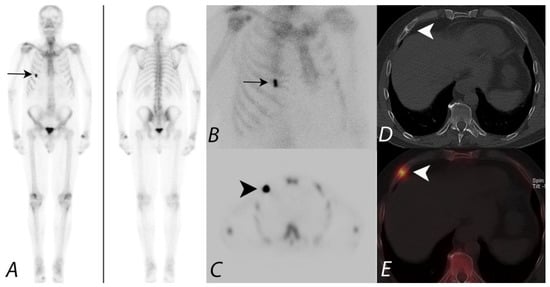

2. Oncologic Applications of Bone SPECT/CT

- Utsunomiya, D.; Shiraishi, S.; Imuta, M.; Tomiguchi, S.; Kawanaka, K.; Morishita, S.; Awai, K.; Yamashita, Y. Added value of SPECT/CT fusion in assessing suspected bone metastasis: Comparison with scintigraphy alone and nonfused scintigraphy and CT. Radiology 2006, 238, 264–271. [Google Scholar] [CrossRef]

- Strobel, K.; Burger, C.; Seifert, B.; Husarik, D.B.; Soyka, J.D.; Hany, T.F. Characterization of focal bone lesions in the axial skeleton: Performance of planar bone scintigraphy compared with SPECT and SPECT fused with CT. AJR Am. J. Roentgenol. 2007, 188, W467–W474. [Google Scholar] [CrossRef]

- Horger, M.; Eschmann, S.M.; Pfannenberg, C.; Vonthein, R.; Besenfelder, H.; Claussen, C.D.; Bares, R. Evaluation of combined transmission and emission tomography for classification of skeletal lesions. AJR Am. J. Roentgenol. 2004, 183, 655–661. [Google Scholar] [CrossRef] [PubMed]

- Römer, W.; Nömayr, A.; Uder, M.; Bautz, W.; Kuwert, T. SPECT-guided CT for evaluating foci of increased bone metabolism classified as indeterminate on SPECT in cancer patients. J. Nucl. Med. 2006, 47, 1102–1106. [Google Scholar] [PubMed]

- Barwick, T.; Gnanasegaran, G.; Rashika, F.; Mohan, H.K. The use of 99mTc-MDP SPECT/CT in the evaluation of indeterminate bone lesions on whole body planar imaging in cancer patients. Eur. J. Nucl. Med. Mol. Imaging 2008, 35 (Suppl. 2), S155. (In abstract) [Google Scholar]

- Helyar, V.; Barwick, T.; Livieratos, L.; Gnanasegaran, G.; Clarke, S.E.; Fogelman, I. The added value of multislice SPECT/CT in patients with equivocal bony metastasis from carcinoma of the prostate. Eur. J. Nucl. Med. Mol. Imaging 2010, 37, 706–713. [Google Scholar] [CrossRef] [PubMed]